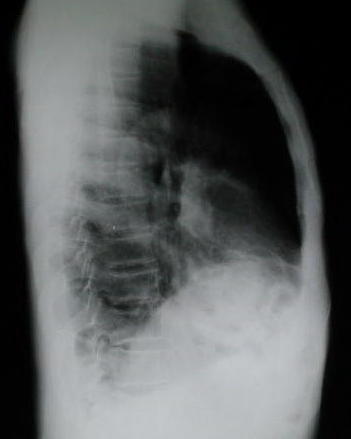

Radilogia Tórax lateral Izquierda

• Una radiografía torácica anormal, en octubre del 1999, reportada inicialmente como reacción pleural de tipo residual, en evaluación traumatológica por disfunción de la articulación del tobillo izquierdo sugiere evaluación neumonológica, los nuevos estudios radiológicos del tórax demuestran patología caracterizada radiopacidad basal derecha con borramiento del hemi diafragma e imágenes de aspecto hidroaereo que plantea la posibilidad de una hernia diafragmática de contenido gastrointestinal de probable etiología pos traumática.

• Puede observarse en los estudios, la hiperplasia funcional compensatoria del pulmón Izquierdo

También puede observarse la hiperplasia compensatoria del pulmón Izquierdo.